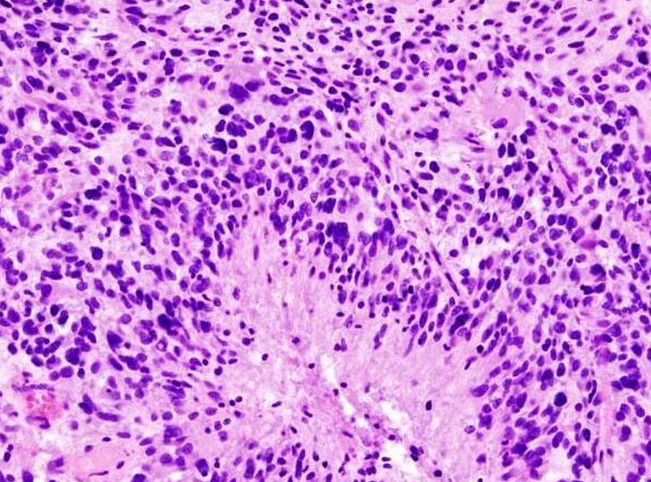

近日,来自美国西北大学的研究人员通过研究利用球形核酸开发出了首个能够用于人类机体全身性治疗的药物,目前这种球形核酸药物已经获得FDA批准,并且作为一种试验性新药正在处于多形性胶质母细胞瘤的早期临床试验中。

这种新药能够跨越血脑屏障直接进入动物模型大脑的肿瘤患处,在肿瘤位点该药物能够关闭关键的促癌基因的表达,目前正在进行的0期临床试验就在调查该药物是否能够直接到达人类机体的肿瘤位点。治疗胶质母细胞瘤的药物代表了一类革命性的新型药物,研究者表示,这种新型的球形核酸平台还能够用于对其它神经变性疾病进行研究,比如阿尔兹海默病和帕金森疾病,其能够通过类似的作用机制来关闭诱发多种神经变性疾病的基因的表达。

通常研究人员利用化疗、放疗和外科手术的方法来治疗胶质母细胞瘤患者,但针对该疾病目前并没有有效的治愈手段,在美国每年大约30000名个体会被诊断为恶性脑癌,而且患者的预期寿命仅为14-16个月。研究者Priya Kumthekar教授说道,我们迫切需要一种能够治疗这种恶性疾病的有效疗法,这项研究中,我们招募了肿瘤复发的患者以及肿瘤移除的候选者进行研究,在患者进行外科手术之前首先通过静脉注射这种新型药物,当肿瘤被移除后,我们将会对肿瘤的药物成分进行研究确定这种新型药物是否能够有效跨越患者的血脑屏障对肿瘤实施精准打击。